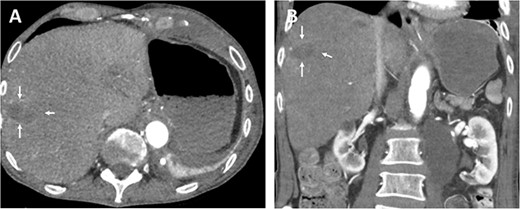

Various antibiotics were started, including meropenem 1 g every 8 hours, vancomycin 1 g every 12 hours, and cefuroxime 500 mg every 8 hours. Computed tomography performed showed occlusion of the celiac trunk and the superior mesenteric artery with prominent collateralization through the inferior mesenteric artery (Fig. 2). The intrahepatic portal vein was patent. In addition, hypodense lesions were found in the liver, which most closely corresponded to hepatic ischemia. The indication for surgical reconstruction was made. We performed an antegrade visceral reconstruction with a bifurcated 12-6 mm Dacron graft from the supra-celiac aortic donor to the superior mesenteric and celiac arteries without any complications.

Preoperative axial (A) and coronal (B) CT angiographic images demonstrate hypoenhancement of all of the hepatic parenchyma and hypodense, hepatic lesion measuring 48 × 47 × 34 mm in the segment V and VI (arrows). (C) 3D reconstructed CT angiography shows occlusion of the celiac and superior mesenteric arteries (thick arrows) and hypertrophy of the inferior mesenteric artery and artery of Drummond (thin arrow).